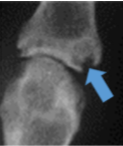

Psoriatic Arthritis

Pencil in cup deformity